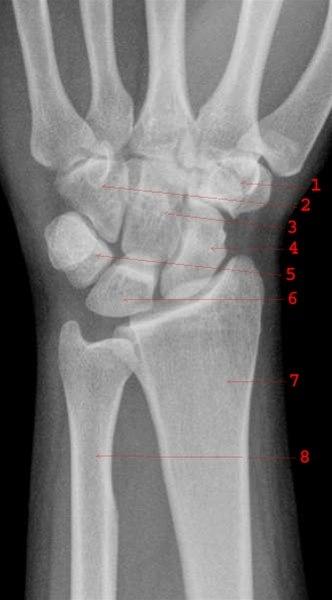

Håndledd front

Normalt håndledd

1. Os trapezium

2. Os hamatum

3. Os capitatum

4. Os scaphoideum

5. Os triquetrum

6. Os lunatum

7. Radius

8. Ulna